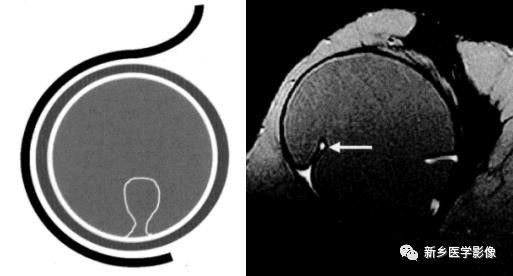

肺实变与肺不张的CT鉴别诊断